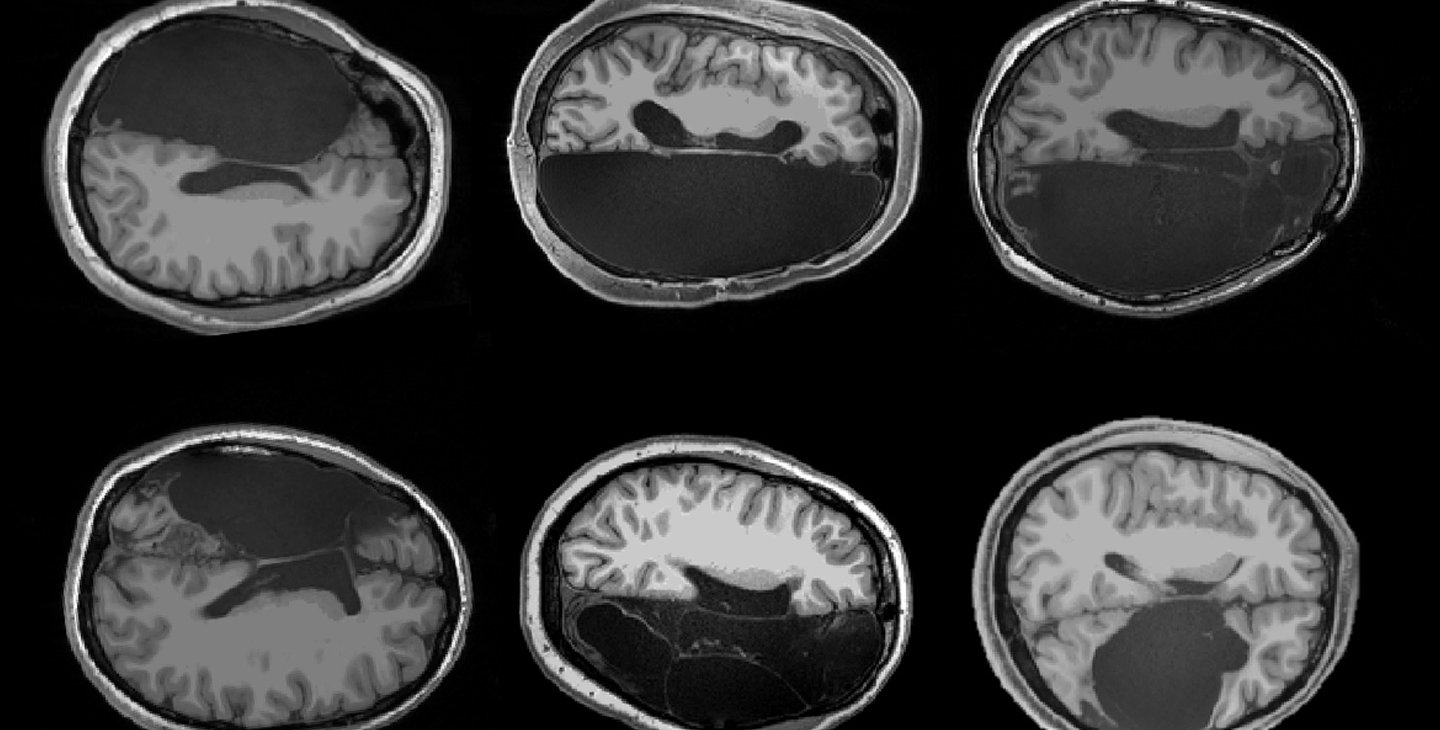

In a new study in the journal Cell Reports, neuroscientists at Caltech describe an investigation of six of these rare patients that offers new insights into how human brains adapt to such extreme changes. The research team performed magnetic resonance imaging (MRI) scans on the patients, all of whom received the surgeries as children and now have relatively normal cognitive abilities. The patients' scans were compared to those of healthy individuals.

Researchers found that adults who had one brain hemisphere removed in childhood (hemispherectomy) showed remarkably preserved organization of functional brain networks in the remaining hemisphere.